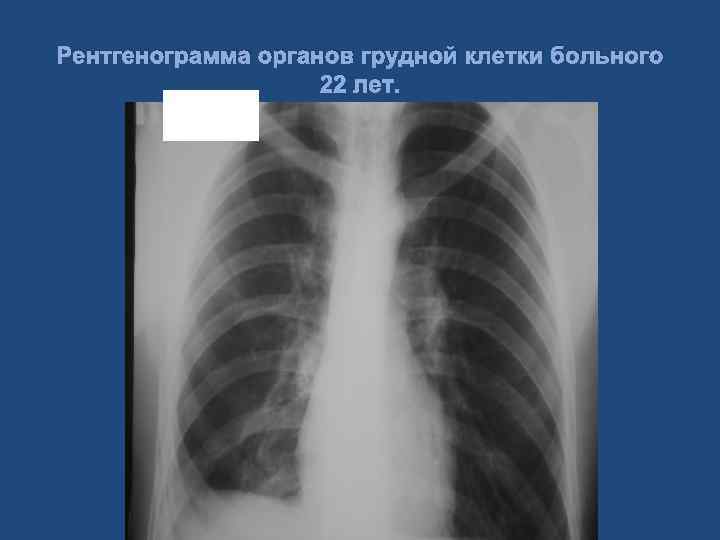

Клиническое наблюдение. Больной 22 лет. Диагноз: Тяжелая сочетанная травма. Тупая травма грудной клетки, двусторонний посттравматический гемопневмоторакс. Тупая травма живота, множественные разрывы правой доли печени, гемоперитонеум. Геморрагический шок Ш ст. 63

Рентгенограмма органов грудной клетки больного 22 лет.